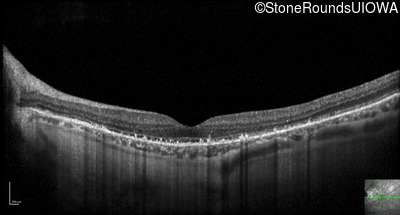

Optical Coherence Tomography - Left - 20/25 +3

Exemplar / OCT Stack

OCT Stack